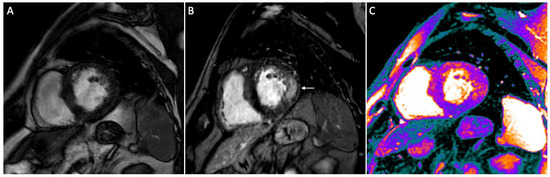

| Nappi [56] | 2015 | Assessment of early car-diac involvement by PET/MR imaging | Prospective, single-center | 13 AFD | Areas with LGE and positive STIR had focal FDG uptake indicating inflammation |